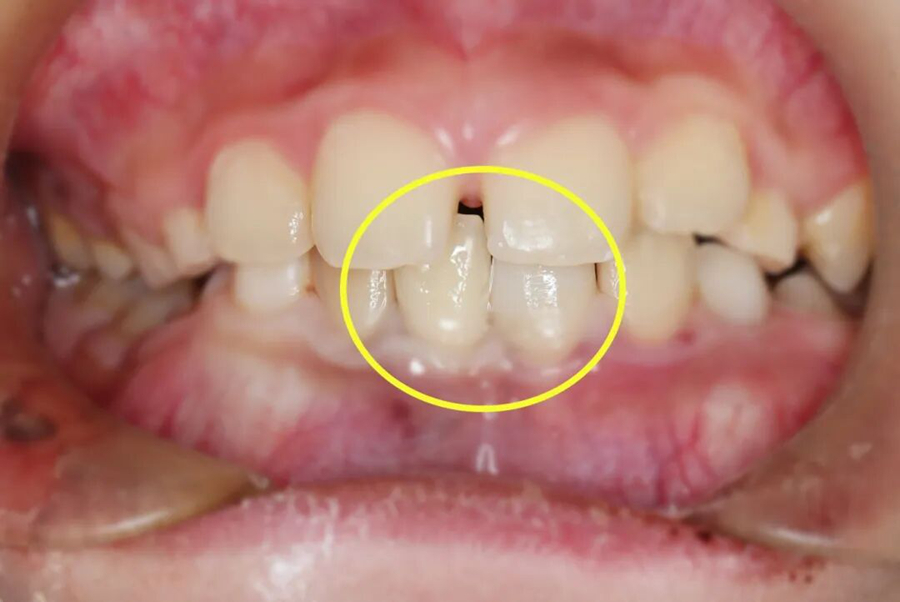

第二步,冠折露髓牙齿修复

针对冠折露髓的牙齿,救治团队在无痛辅助和显微镜下,彻底清除根管内的感染组织,进行严密的三维根管填充,建立无菌的内部环境。紧接着采用仿生树脂材料,通过分层分色堆塑技术,精准复原牙齿的天然形态和色泽,既解决了感染隐患,又恢复了牙齿的美观和咬合功能。